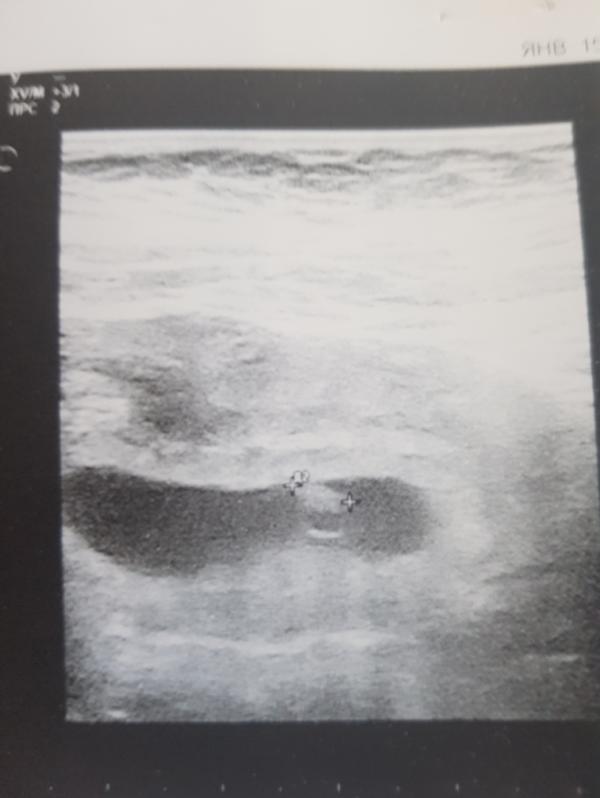

Ну вот и первое фото малыша😊 (не пугайтесь, это не глаза лягушонка🙈, это узист крестиками отмечал размеры). Все у нас хорошо, плод один, соответствует 6-7 неделям беременности, на учет еще не вставала.